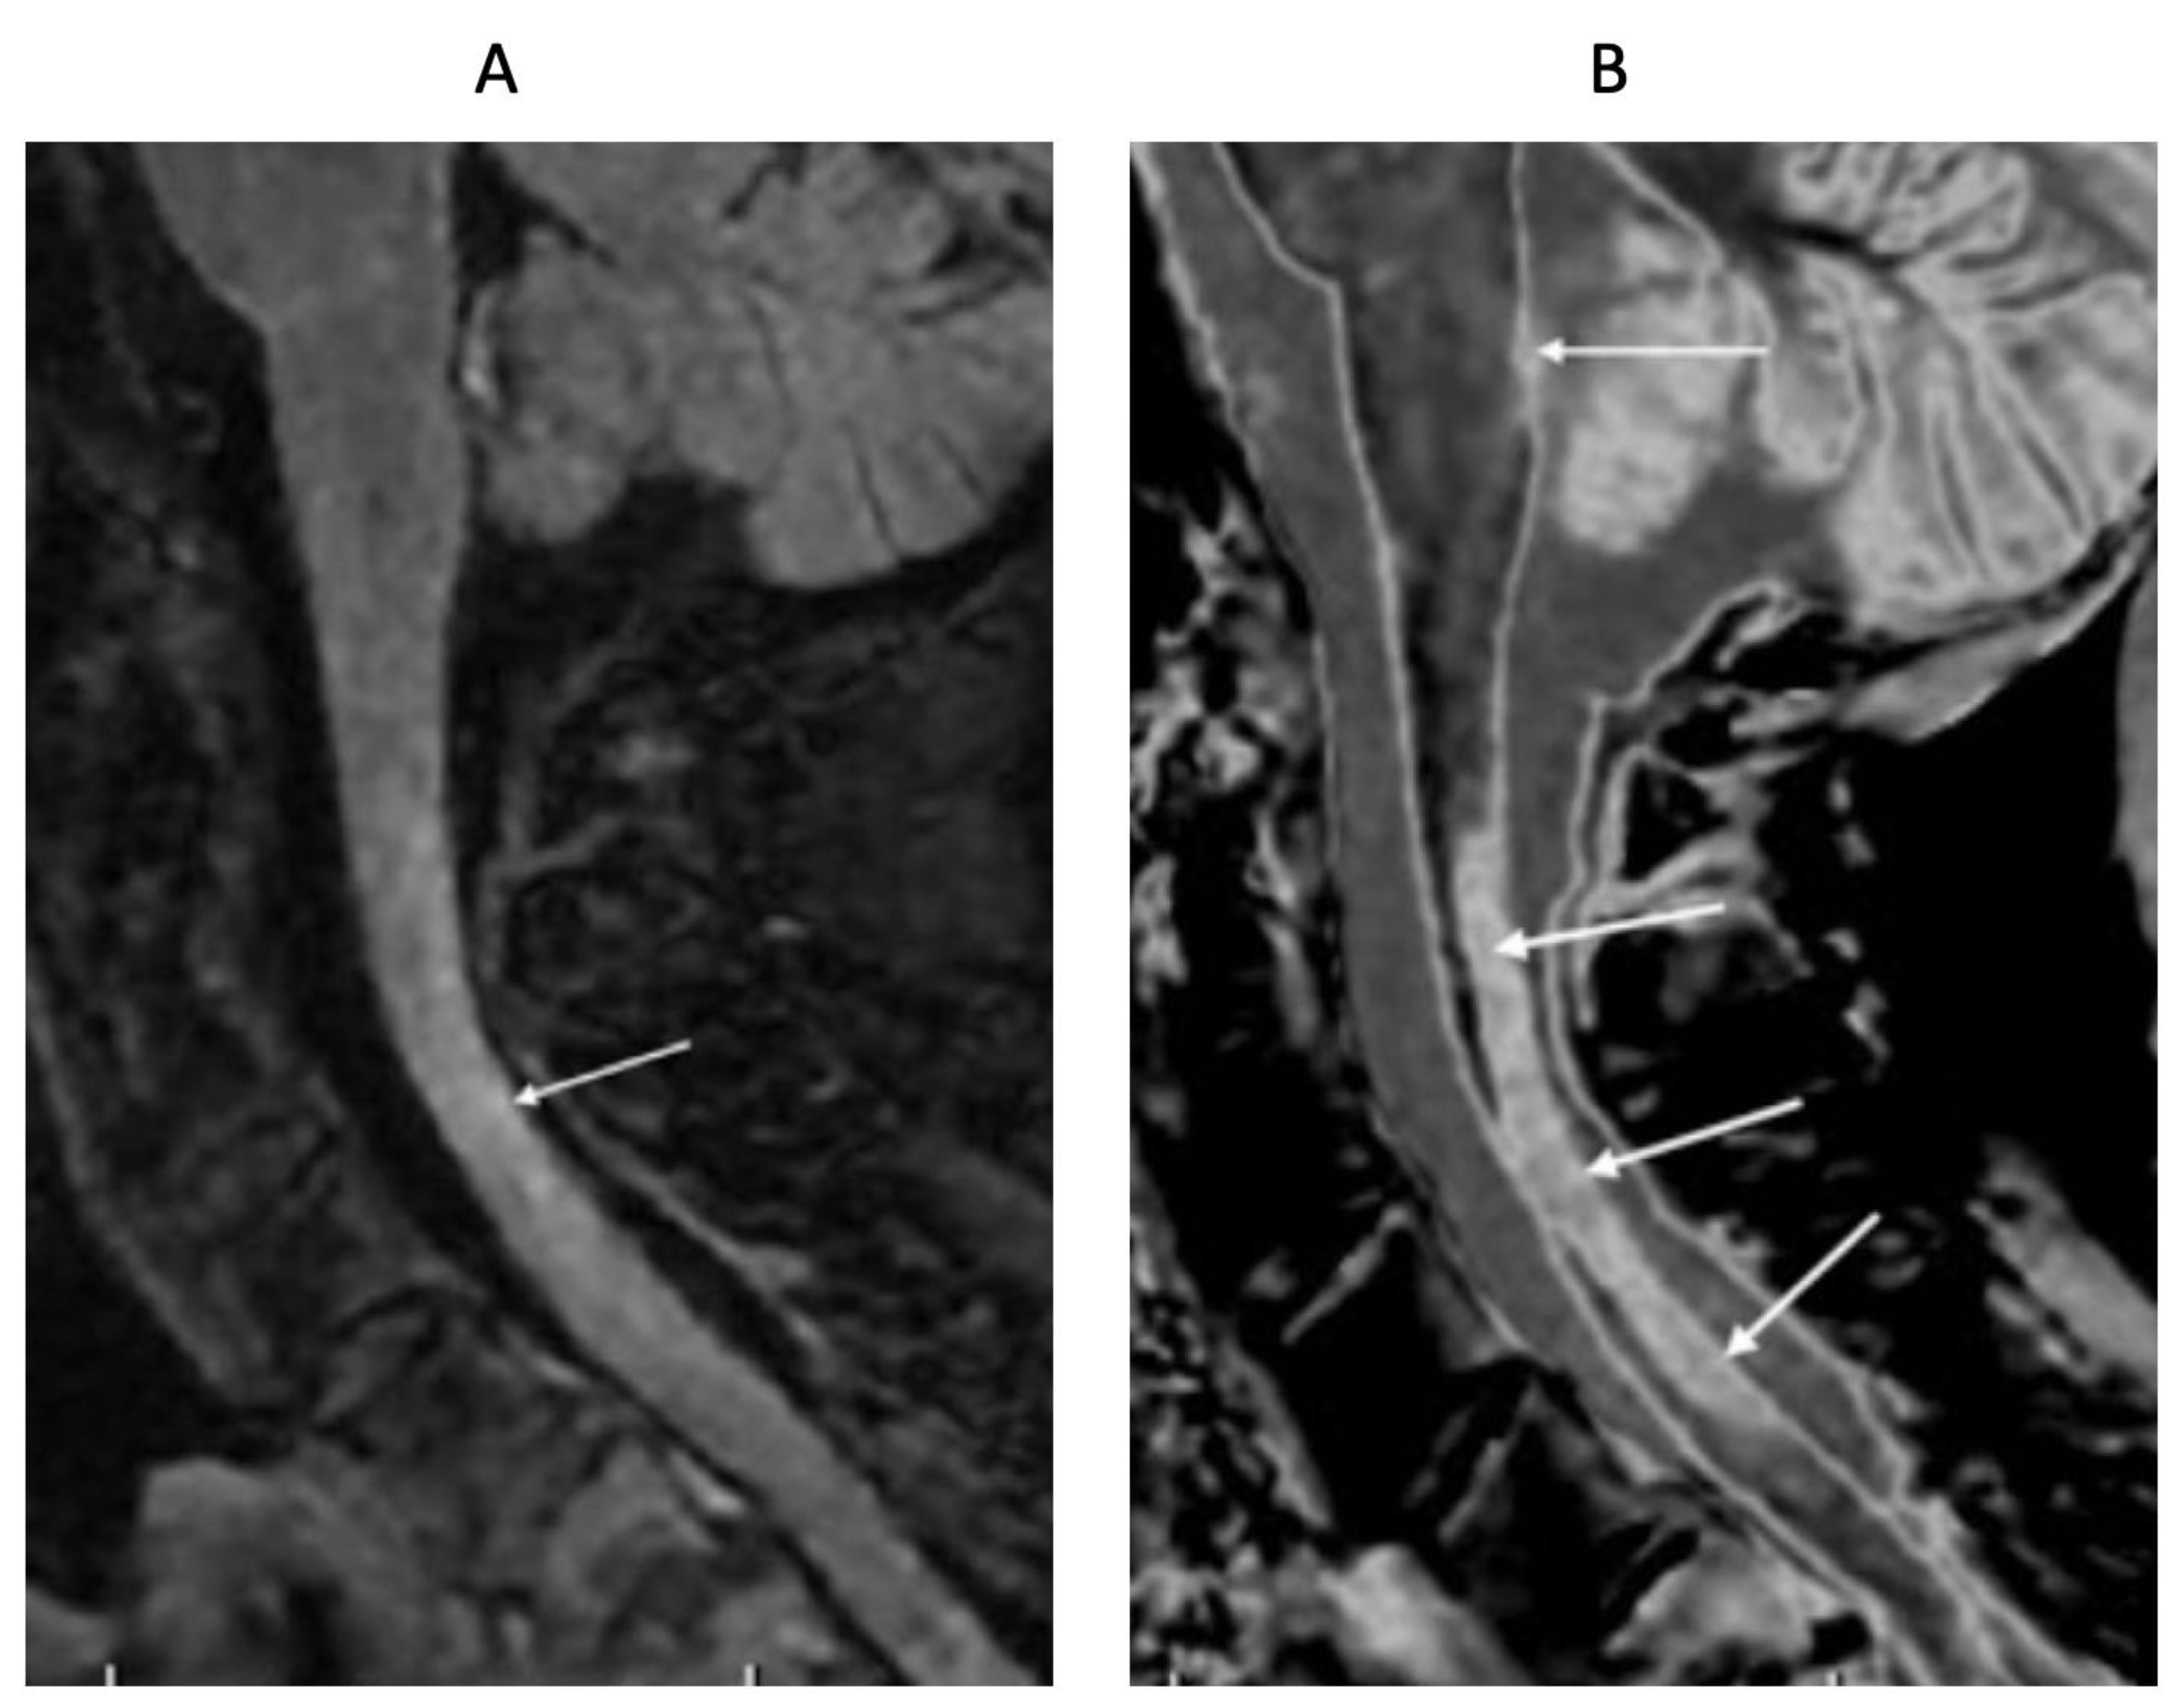

- Ultra-high contrast MRI using bipolar filters (BLAIRs) can show abnormalities with very high contrast where little or no change from normal is seen with common conventional state-of-the-art sequences.

- The abnormalities shown with ultra-high contrast are due to small changes in tissue properties such as T1 and T2 in disease. This is complementary to existing sequences which show abnormalities due to larger changes in T1 and T2 in disease.

- At boundaries between tissues and fluids on ultra-high contrast images there is frequently an increase in contrast and an increase in the spatial resolution of that contrast.

- Extensive abnormalities were seen in mild traumatic brain injury, multiple sclerosis and white matter associated with cerebral tumours in the absence of changes in T2-weighted spin echo or T2-FLAIR images.